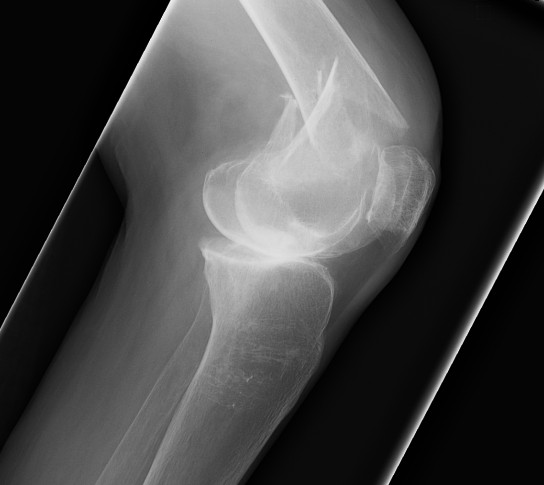

AO Type A: Supracondylar / Extra-condylar

Xray